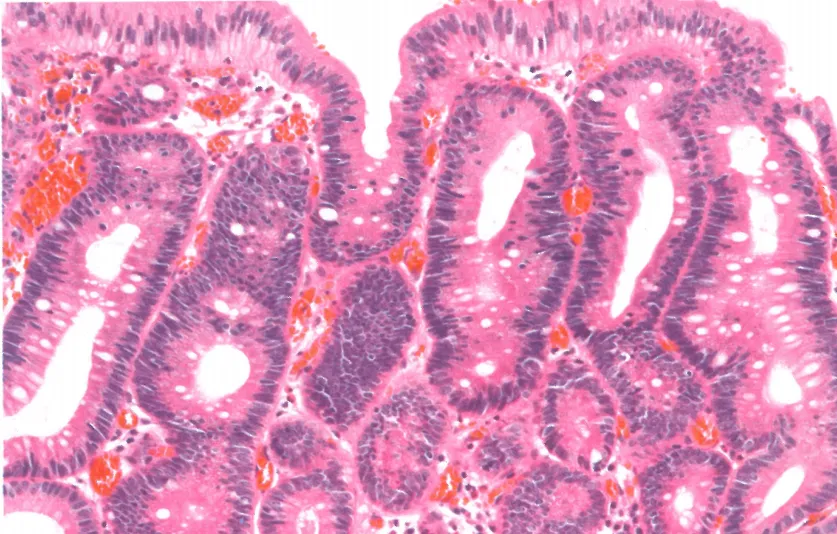

肠型低级别异型增生:可见肠型分化的高柱状细胞,细胞核呈细长形态且基本位于细胞中央

胃型低级别异型增生:小凹分化的高柱状细胞;细长细胞核位于基底